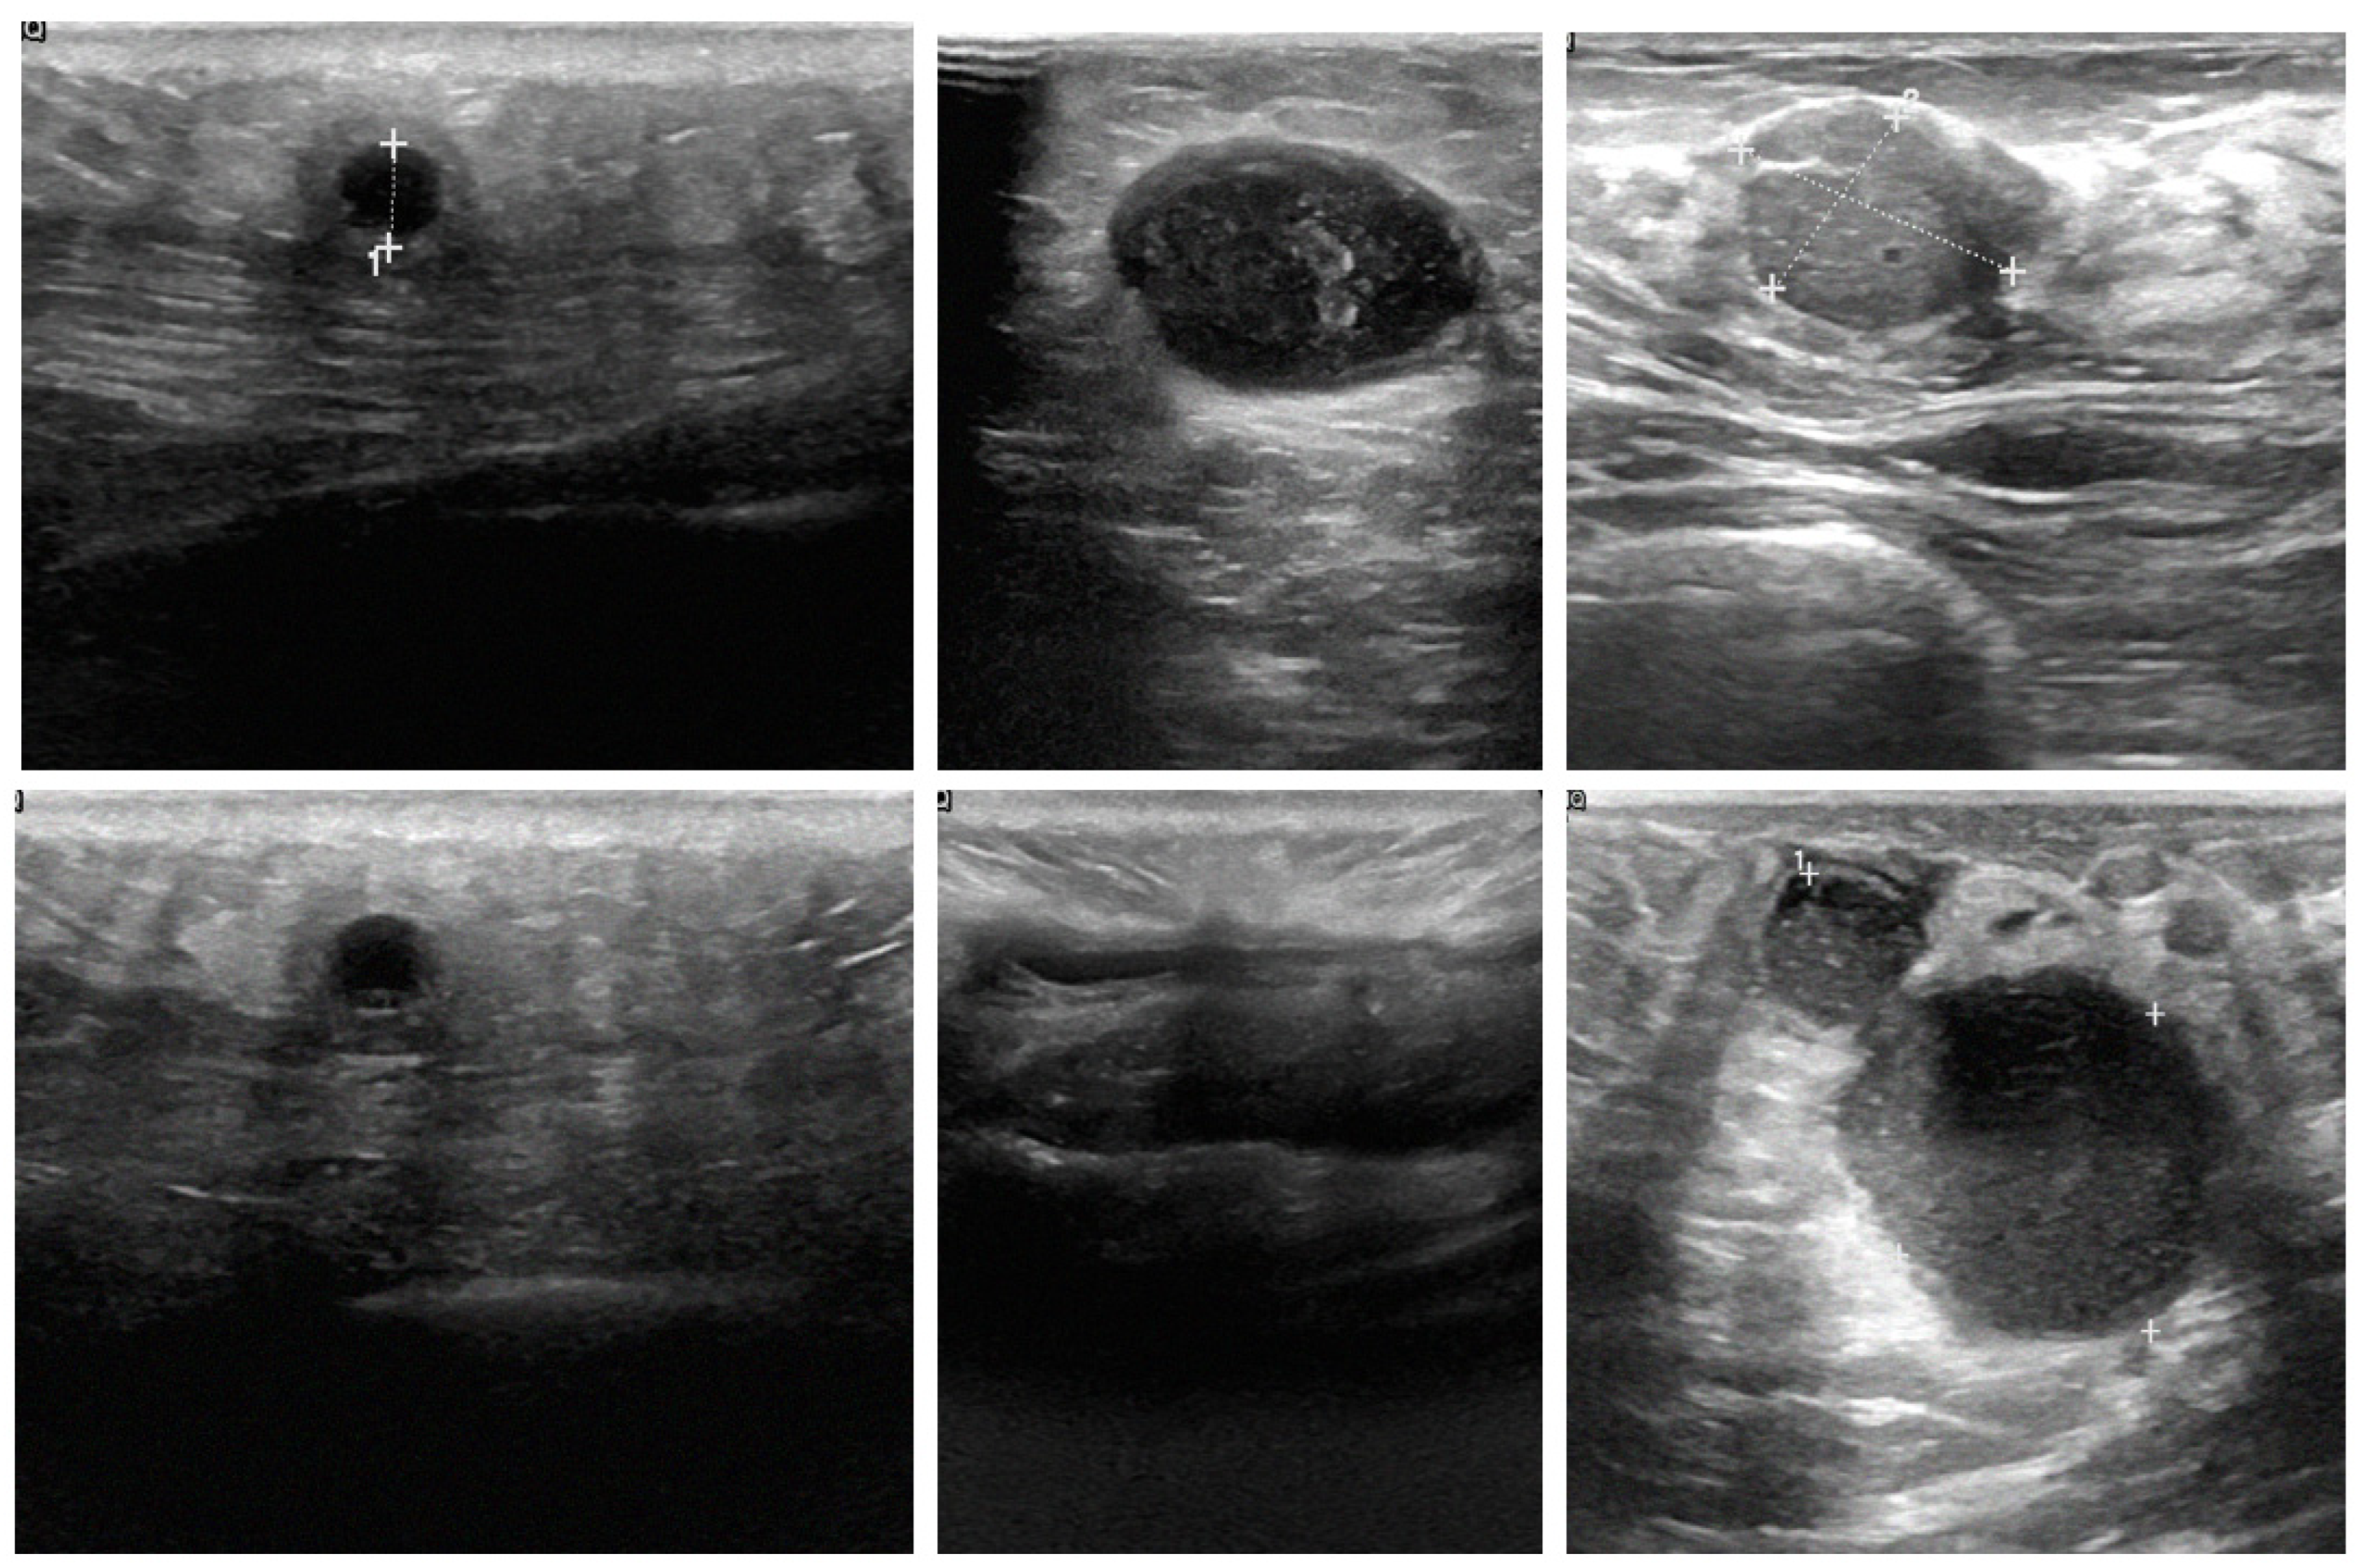

This study utilized breast images from three prominent public databases: the Radiological Society of North America (RSNA), the Polish Academy of Sciences (PAS), and Kaggle (Table 1). Table 1 provides a summary of the data sources and imaging modalities used in this study and the dataset distribution, both before and after data augmentation. The RSNA dataset contains mammography images, with 1200 benign and 1158 malignant cases, and the images were resized to 256 × 256 pixels. The Kaggle dataset includes B-mode ultrasound images, with 437 benign and 210 malignant cases, expanded using data augmentation to 1311 benign and 840 malignant cases. The image sizes in this dataset vary between 324 × 510 and 719 × 811 pixels. Similarly, the Polish Academy of Sciences dataset comprises B-mode ultrasound images, with 96 benign and 104 malignant cases originally, augmented to 288 benign and 416 malignant cases, with an image size of 256 × 256 pixels. The overall dataset after augmentation consists of 2799 benign and 2414 malignant images. The table illustrates the diversity of the data sources and modalities used in this study and highlights the role of augmentation in addressing dataset imbalances. The diversity of these datasets allowed for the development of AI models capable of performing well across different imaging modalities and patient populations. The images are categorized by modality and diagnosis: mammography (RSNA) for benign (A–C) and malignant (D–F) cases, sonography-1 (Kaggle) for benign (G–I) and malignant (J–L) cases, and sonography-2 (PAS) for benign (M–O) and malignant (P–R) cases. These images illustrate the diversity of the data sources and imaging modalities utilized for the classification tasks in this research (Figure 2).

Figure 2.

Representative examples of breast imaging modalities used in the study. The mammography (RSNA) for benign (A–C) and malignant (D–F) cases, sonography-1 (Kaggle) for benign (G–I) and malignant (J–L) cases, and sonography-2 (PAS) for benign (M–O) and malignant (P–R) cases.